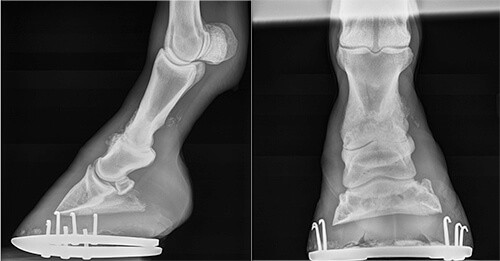

Netty’s pastern arthrodesis was performed by Ortved via an open technique using inverted “T”- and “V”-shaped incisions made across the front of the pastern to access the joint and remove the damaged cartilage. A specialized three-hole locking compression plate was then placed with three transarticular screws across the face of the joint to stabilize it and support healing of the soft tissue around it.

netty3New Bolton Center’s surgeons now routinely use the locking compression plate for arthrodesis, a technology that has emerged within the last 15 years. Traditional non-locking bone plates use normal cortical bone screws that are placed through the plate into the bone, whereas locking compression plates use special screws with heads that secure into the plate itself.

“This creates a much sturdier and more stable fixation, with less potential for movement,” explained Ortved. “In particular, the shorter three-hole locking compression plate implant, with holes that are perfectly positioned to place across the pastern joint, has really helped fine-tune the pastern arthrodesis surgery.”

netty4Once the cast was removed, post-operative radiographs were taken, which confirmed excellent placement of the implant. “At that point he was still recovering quite well, so we sent him home with Aimee to continue his rehab there,” said Ortved.